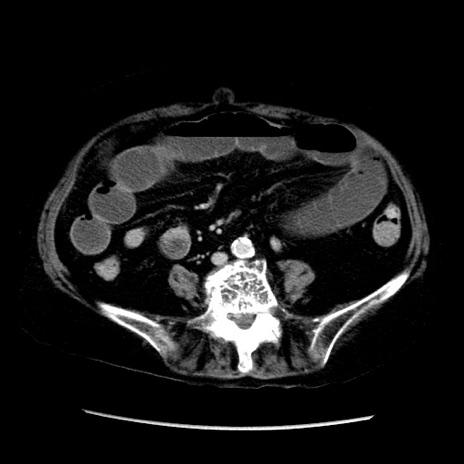

症例14(横断像)

【症例】 90歳代女性

【主訴】 腹痛・嘔吐

【現病歴】今朝から左側腹部痛を認めた。 経過観察していたが、嘔吐を認めたため来院。

【既往歴】 子宮癌術後

【身体所見】 意識清明、BP 127/54mmHg、P 98bpm Sp02 95%(RA)、BT 35.8°C、腹部平坦・軟腸ぜん動音聴取良好、右下腹部圧痛(+) 反跳痛なし

【データ】WBC 9800、CRP 0.46